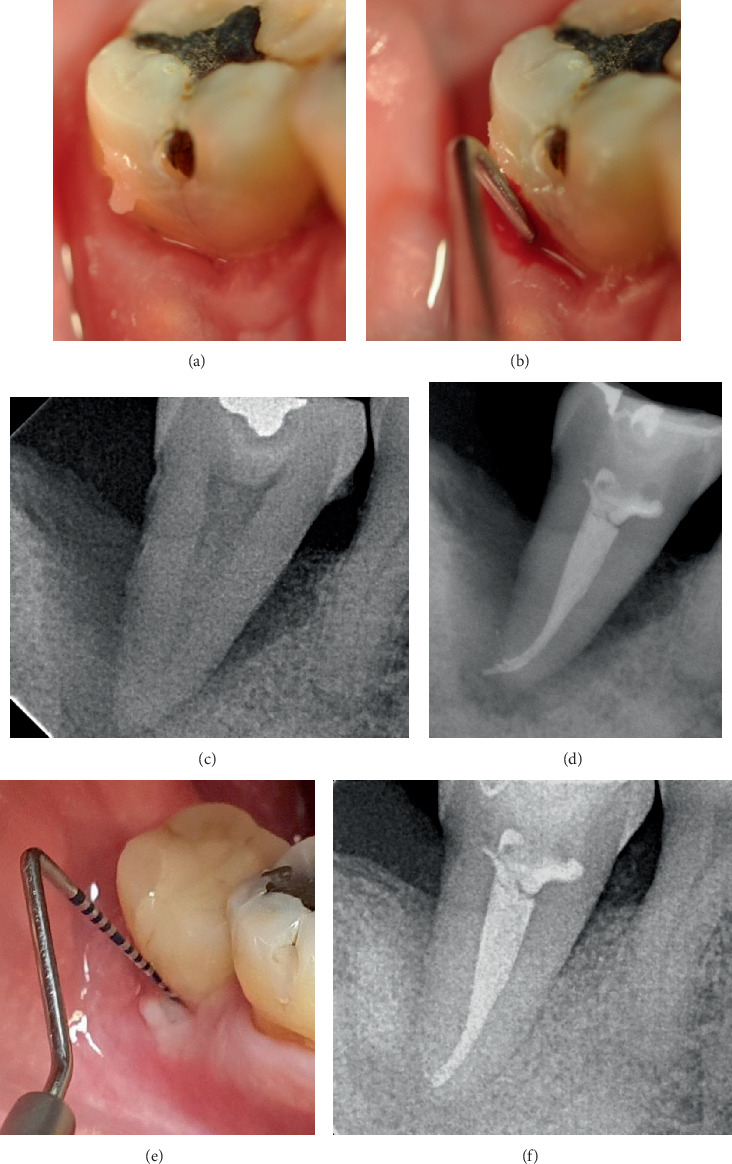

牙周再生(PR)可能是严重受损牙齿的一种可行的治疗选择。本病例系列通过长达13年的随访显示PR的长期益处。5例患者共6颗牙采用PR治疗骨内缺损。治疗方法包括提升粘骨膜瓣,根内固定,并用骨替代物填充骨缺损。PR后,探查深度(PD)明显减少(平均9.5±1.87 mm;p = 0.03),临床附着水平(CAL)也有统计学意义的增加(平均8.33±1.03 mm;P = 0.03)。x线片也证实了缺损部位骨缺损填充(平均9.67±2.25 mm;P = 0.03)。在长达13年的随访中,本病例系列表明,PR可减少PD,且牙龈萎缩最小,CAL增加,缺损部位骨填充,即使是复杂的牙周缺损延伸到根的根尖部分,这表明它是一种有效且可预测的治疗选择。

Periodontal regeneration (PR) could represent a viable treatment alternative for severely compromised teeth. This case series presents the long-term benefits of PR with up to 13 years of follow-up. A total of six teeth in five patients were treated for intrabony defects using PR. The treatment involved the elevation of a mucoperiosteal flap, root instrumentation, and filling the bony defect with bone substitutes. Following PR, a significant reduction in probing depth (PD) was observed (mean 9.5 ± 1.87 mm; p = 0.03) along with a statistically significant gain in clinical attachment level (CAL) (mean 8.33 ± 1.03 mm; p = 0.03). Radiographic bone defect fill at the defect site was also verified (mean 9.67 ± 2.25 mm; p = 0.03). This case series demonstrated that PR led to reduced PD with minimal gingival recession, gain in CAL, and bone fill at defect sites, even in complex periodontal defects extending to the apical portion of the root, over a follow-up period of up to 13 years, indicating it as an effective and predictable treatment alternative.